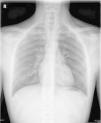

La radiografía de tórax (fig. 1) mostraba enfisema subcutáneo en las regiones cervical, supraclavicular y axilar izquierdas con neumomediastino. La gasometría arterial fue normal.

Ingresa en observación bajo oxigenoterapia (mascarilla reservorio) durante unas horas, en las que se aprecia mejoría clínica con desaparición del dolor y molestias, manteniendo las constantes normales. Doce horas después se realiza una radiografía de control, con clara mejoría.

Dada la buena evolución clínico-radiológica, es dado de alta bajo observación domiciliaria. Tres días después acude a control, asintomático y con radiografía de tórax normal.